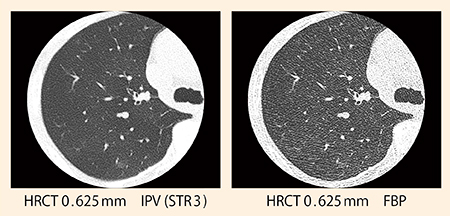

胸部CTはスライス厚0.625mmで撮影し,肺野は1mm,縦隔は5mmで読影している。杉山部長は画質について,「FBPに近い違和感のない画像で十分に満足しています。辺縁部も高精細に描出されていますし,画像ノイズとアーチファクトも抑えられているので,ストレスなく読影できます」と評価する。

画像1:すりガラス状陰影症例

撮影条件120kVp,0.35s/rot,BP1.08,CTDIvol:1.4mGy IPVの使用により,鮮鋭度を保ちながら画像ノイズとアーチファクトを大幅に低減できていることがわかる。